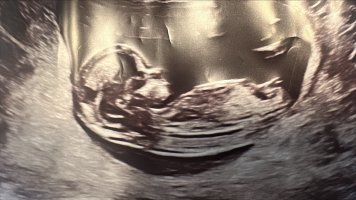

Vil dere gjette ut fra teorien hva kjønnet kan være? blir litt gal og sykehuset ville ikke si det fordi det var for tidlig..

nå har jeg fått bekreftet om at det er liten jenteHar disse ogsåhåper man kan se det på et av bildene hvertfall (alle de er tatt samme dag 12+3) @lyse gul